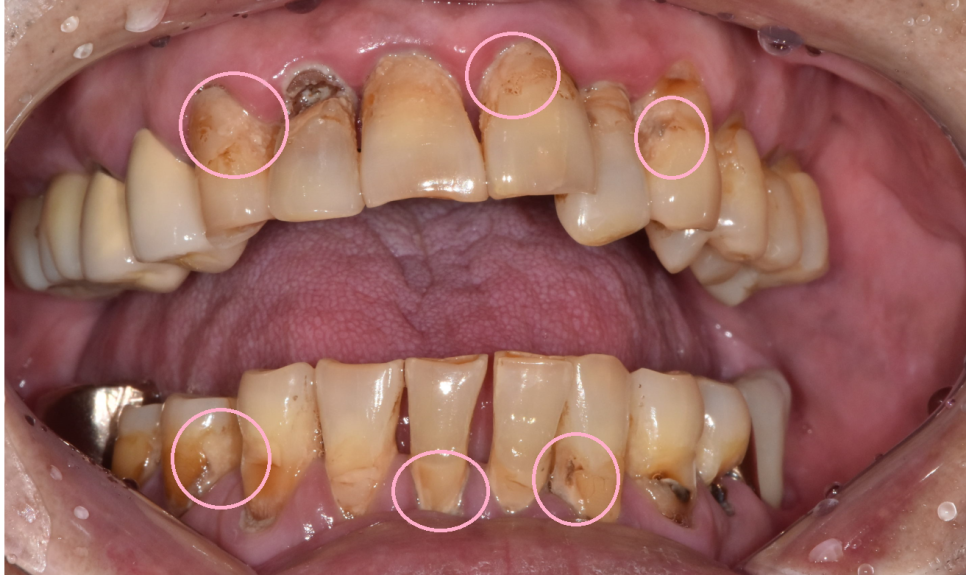

양치도 전반적으로 안되어있어

치태라고 하는 찌꺼기들이 치아 전반적으로 붙어있었습니다.

구강위생이 불량하니 잇몸이 더 빨리 무너졌네요~~

기타 증상으로는 녹아버린 잇몸뼈로

잇몸이 위로 올라가다보니 치아 뿌리 부분이 노출

양치가 안되면서 뿌리부분이 썩고,

전반적으로 파여있는 모습이었습니다.